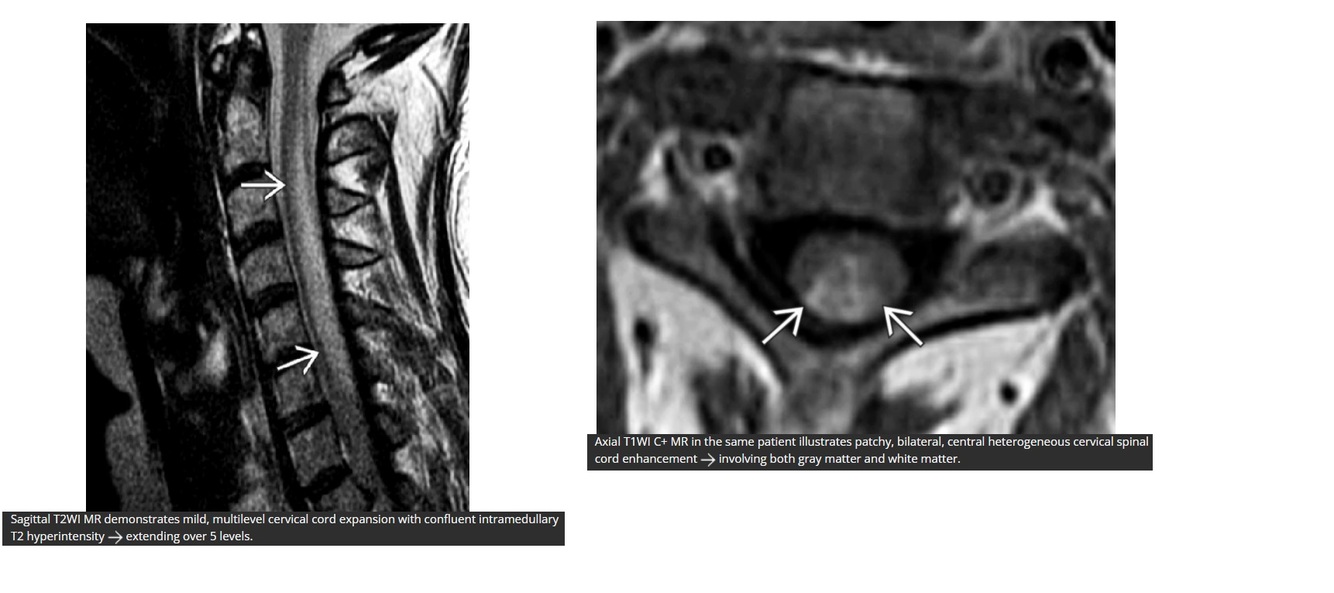

Q

Central cord lesion > 2 vertebral segments in length with eccentric enhancement in thoracic region.

A

Transverse myelitis

At least 2/3 of cross section of the cord affected (WM and GM).

‘Expansion of central cord’

Acute partial = lesions < 2 segments

Acute complete = lesions > 2 segments

** Acute partials are higher risk for developing MS**

DDx MS

- smaller usually confined to 1-2 vertebral levels

- affecting less than half of the cross-sectional area of the cord

DDx ADEM

-usually demyelination in WM of the brain

- if in spine, spares grey matter